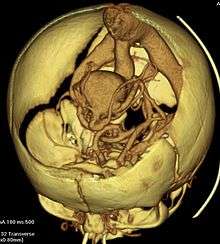

Vein of Galen aneurysmal malformations (VGAM) and Vein of Galen aneurysmal dilations (VGAD) are the most frequent arteriovenous malformations in infants and fetuses.[1] VGAM consist of a tangled mass of dilated vessels supplied by an enlarged artery.[2] The malformation increases greatly in size with age, although the mechanism of the increase is unknown.[2] Dilation of the great cerebral vein of Galen is a secondary result of the force of arterial blood either directly from an artery via an arteriovenous fistula or by way of a tributary vein that receives the blood directly from an artery.[1][2] There is usually a venous anomaly downstream from the draining vein that, together with the high blood flow into the great cerebral vein of Galen causes its dilation.[3] The right sided cardiac chambers and pulmonary arteries also develop mild to severe dilation.[4]

Treatment depends on the anatomy of the malformation as determined by angiography or Magnetic Resonance Imaging (MRI).[3]